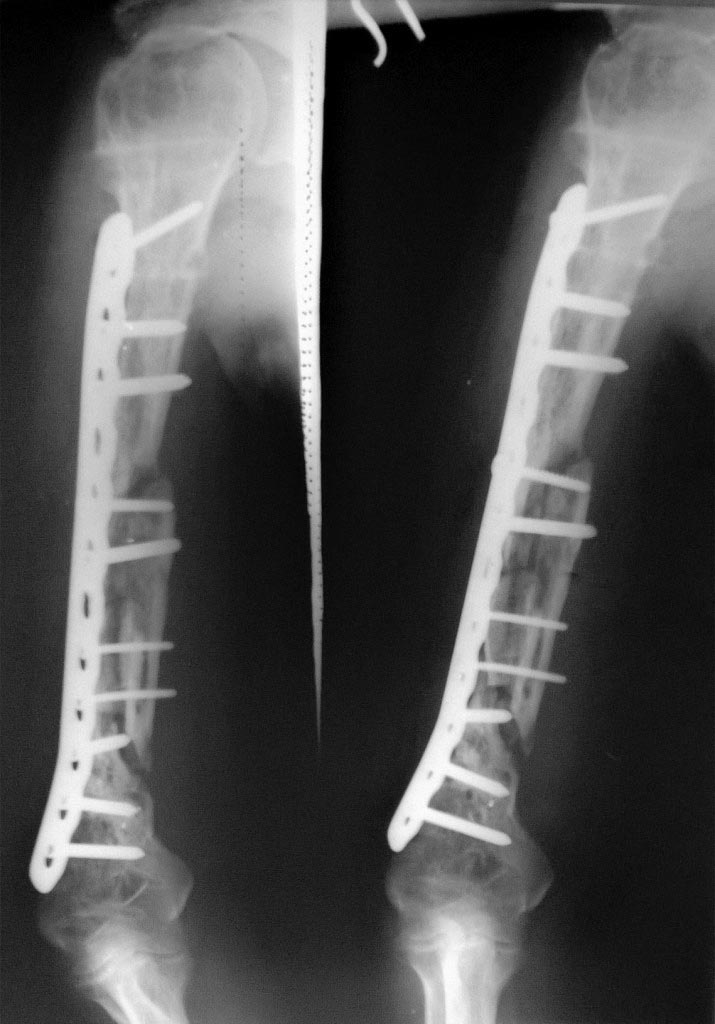

Большое спасибо за ответ и фото. Позволю себе выложить их здесь.

1 до операции

1а до операции

2 до операции

3 схема вид отломков после удаления пластины

4 вид отломков после удаления части стенки "бокала"

5 вид отломков при сохранении одной из стенок

6 остеосинтез стержнем

7 схема укладки трансплантатов

8 фото момент укладки трансплантатов в дефект

9 контрольная рентгенограмма после операции

10 рентгенограмма через год

11 остеосинтез пластиной с костной пластиной

(спицы слева от пластины фиксируют тр-т из лопатки)

12 пластина

13 рентгенограмма через год

14 клинически через год (может и выше)

|

Прооперировали пациента. Выделен лучевой нерв, мобилизованы концы отломков, высечены рубцы, перелом фиксирован LCP пластиной. Костная аутопластика из крыла подвздошной кости.